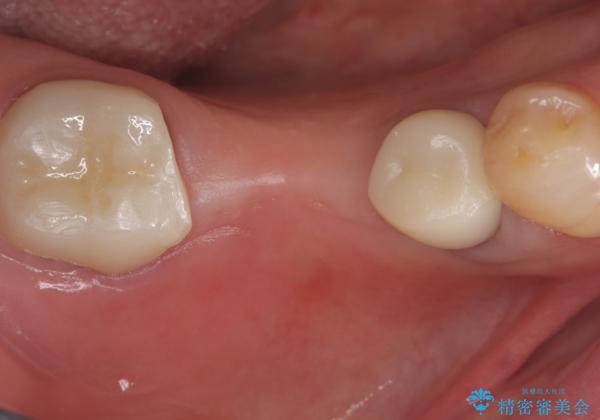

セラミックに比べ、破折リスクの少ない金属を使用したブリッジでのやり替えとなりました。

両支台歯が失活歯のため、どちらかもしくは両方の歯が破折した際、再度ブリッジを除去した治療が必要になるリスクとインプラント治療のご提案もさせていただきましたが、ブリッジでの治療を希望されました。